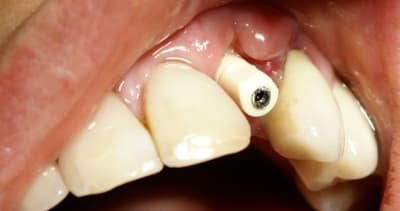

Tout à fait d'accord growler et c'est d'ailleurs ce que l'on peut voir sur le cas suivant. Fracture radiculaire, aucune infection periradicualire. Extraction et implantation immediate. Espace existant entre l'implant et l'alvéole est comblé par du BioOss. Un logement sous gingival est formé en vestibulaire et palatin de facon à pouvoir recouvrir le tout par BioGide et un conjonctif enfoui.

L'implant est de 15mm mais l'alvéole était large et 50% environ de la surface implantaire n'était en contact qu'avec du BioOss. J'ai pour cela préféré enfouir.